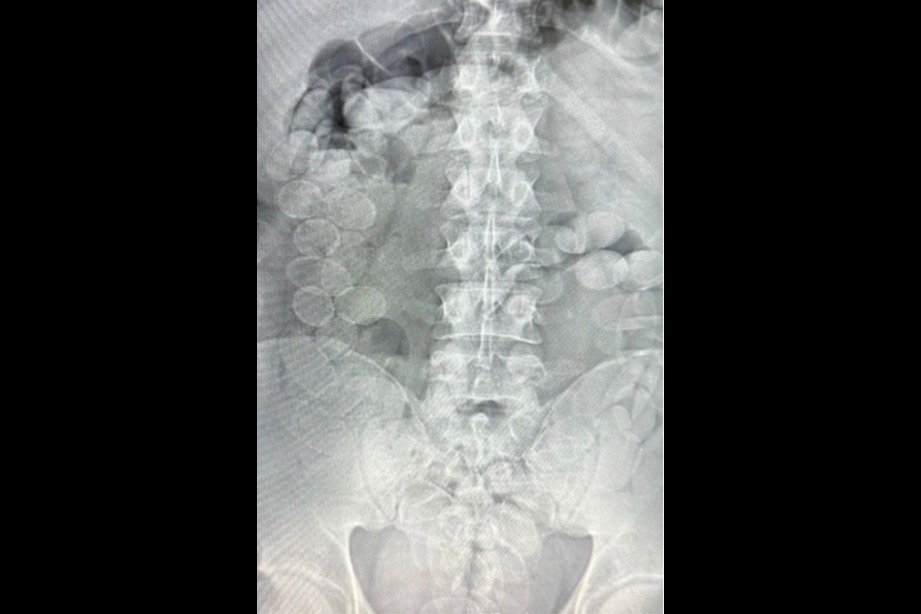

Tras ser trasladados a un hospital de Ceres, estudios médicos confirmaron la presencia de los envoltorios en sus organismos. En total, expulsaron 185 cápsulas: 93 correspondientes a Quispe Carmona (1.239 gramos) y 92 a Rocha Risco (1.212,3 gramos). El cargamento total alcanzó los 2.451,3 gramos de cocaína con una pureza promedio del 85,17%, lo que habría permitido producir más de 20 mil dosis.